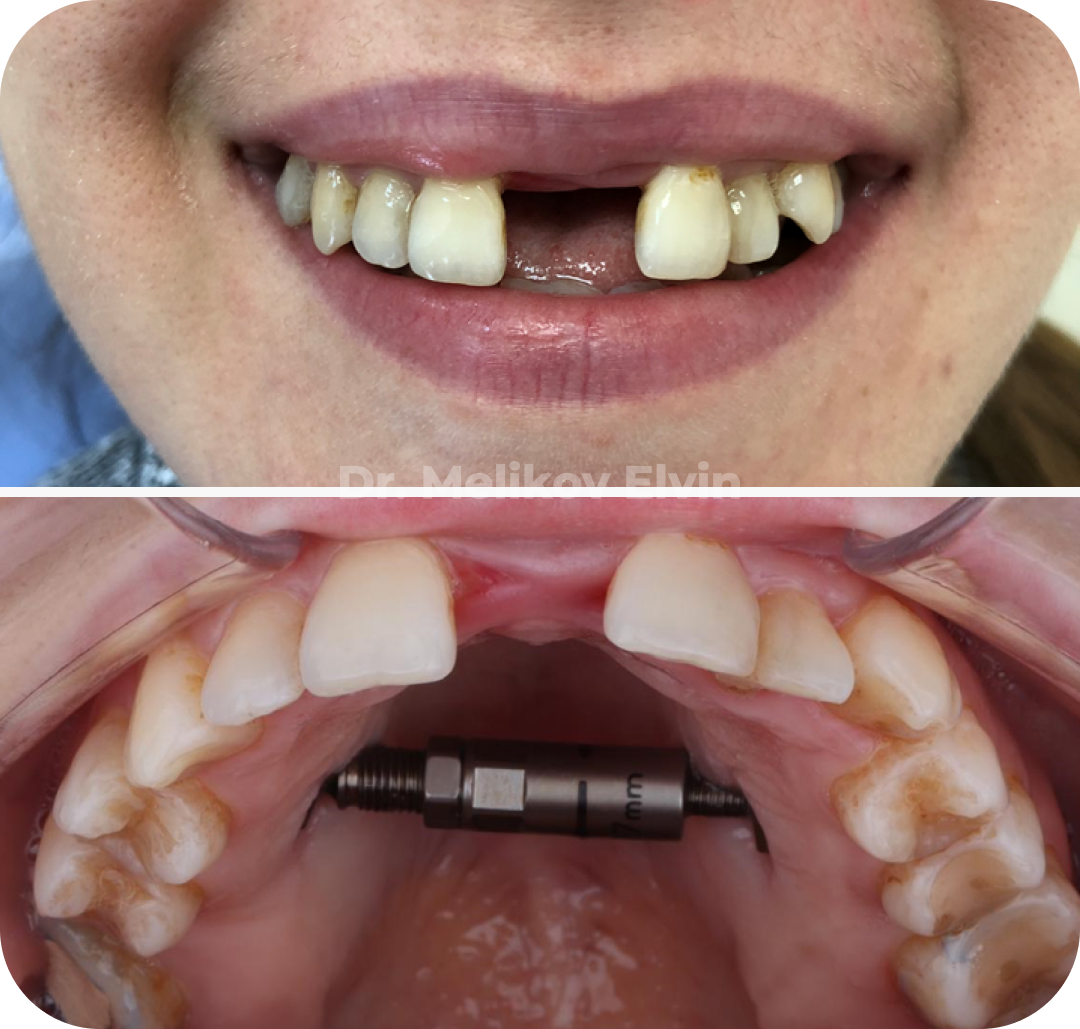

Фотографии до операции по расширению верхней челюсти.

На этапе расширения.